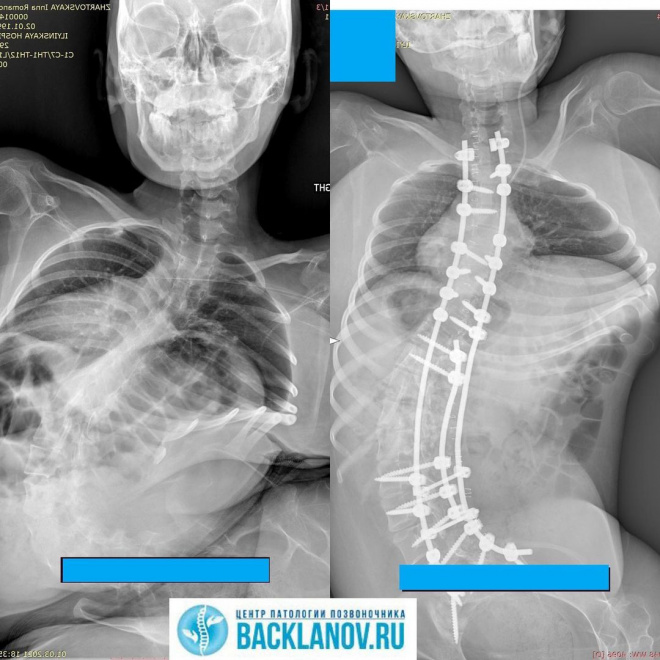

Операция прошла хорошо, были небольшие осложнения, но не критично.

Спасибо всем большое, за то, что это случилось! Я прибавила в росте примерно 25-30 см, что накладывает некоторые неудобства сейчас - к такой высоте нужно привыкнуть!

Теперь я ровно сижу, после операции было больно и я не могла сидеть больше получаса, но сейчас уже могу спокойно сидеть по 10-12 часов в день. Реабилитация идёт успешно и недавно я уже смогла выйти на работу а также сдать экзамены в университете.